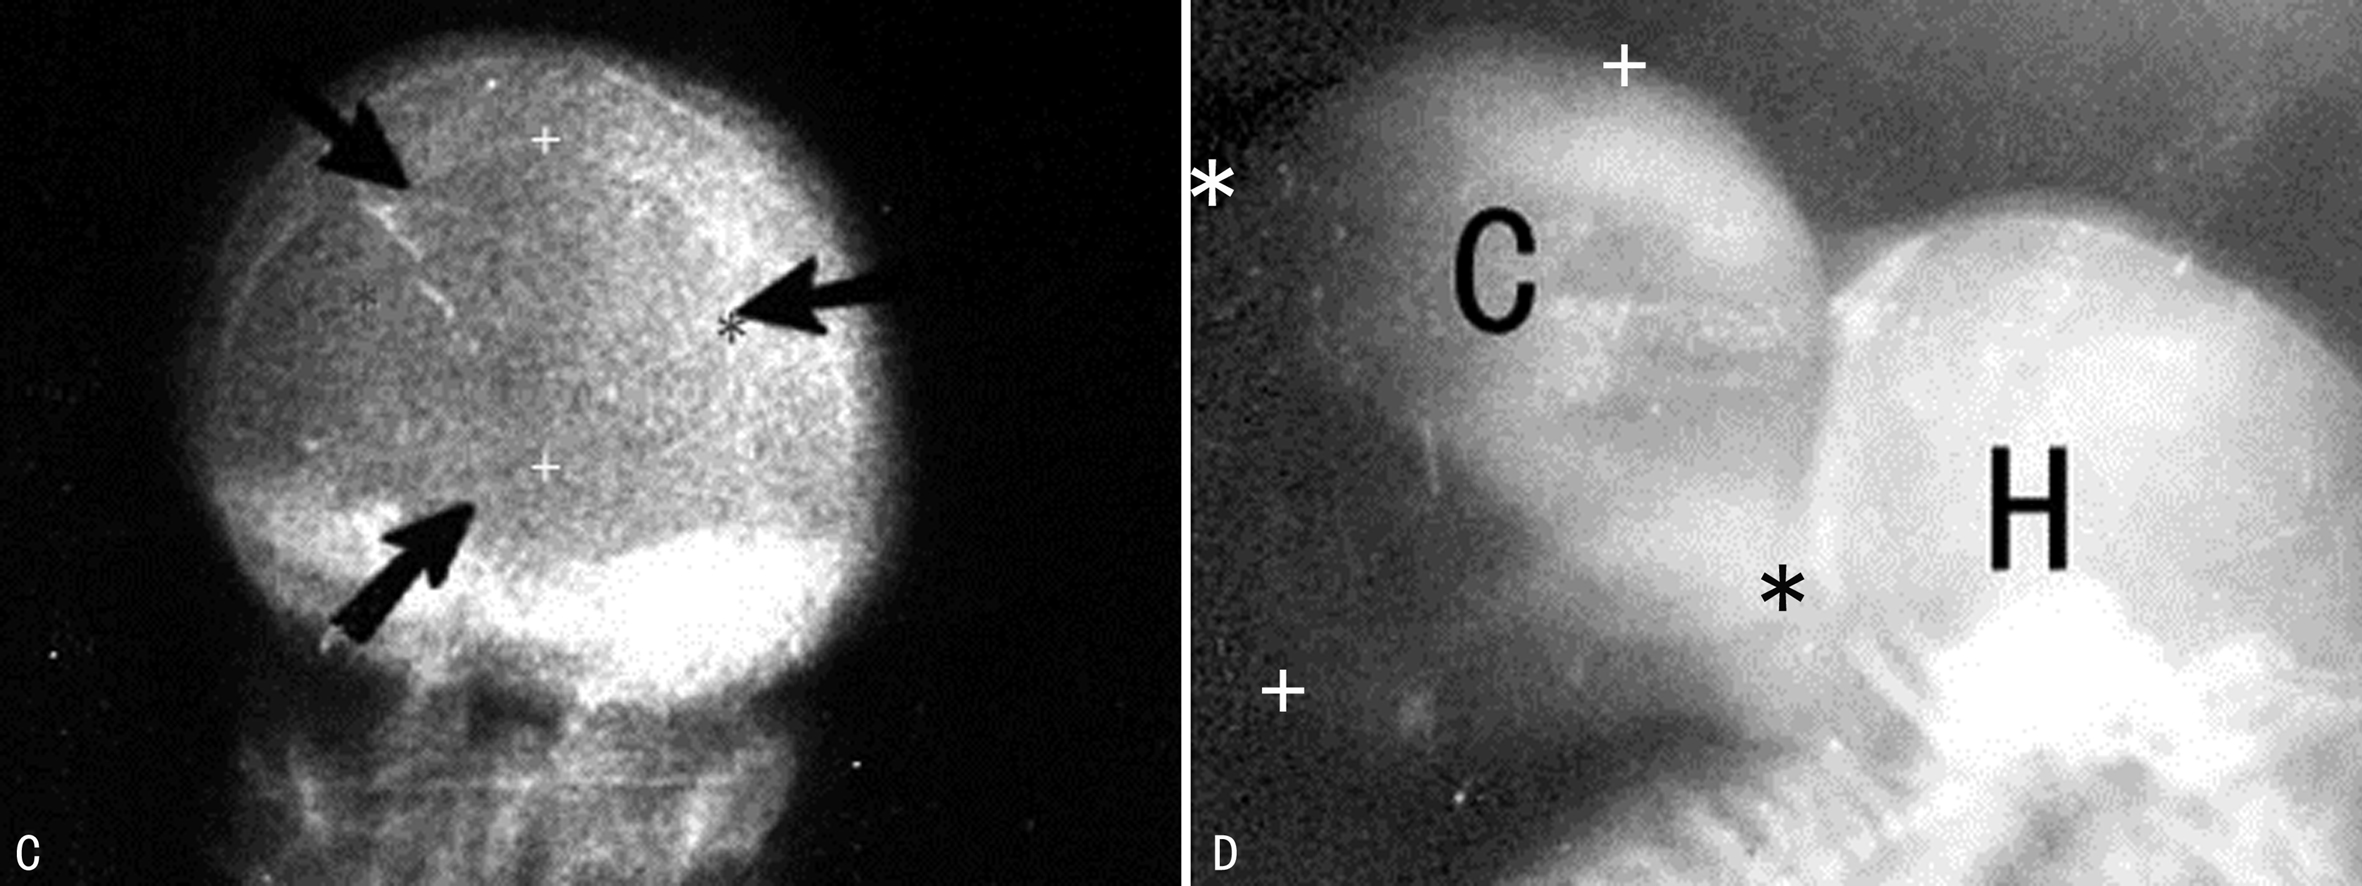

图3 CD胎儿巨大脑膜脑膨出出生后X检查